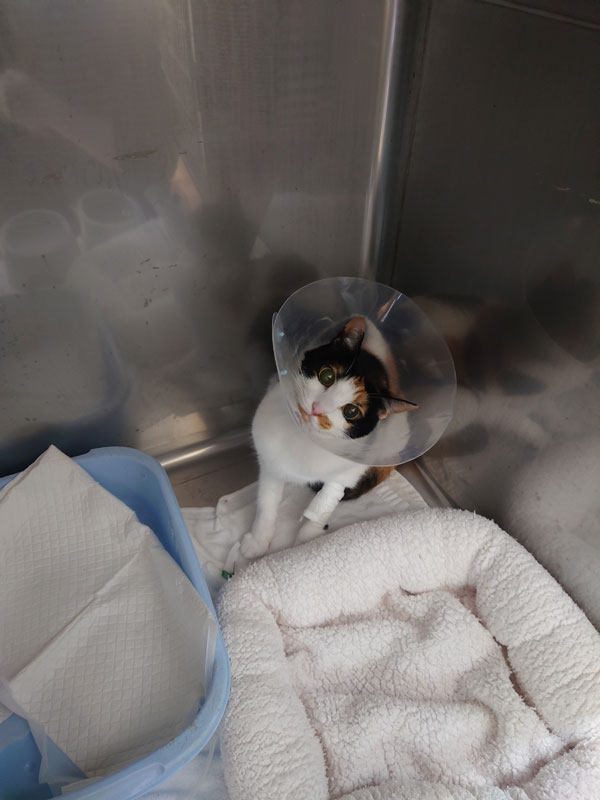

まあコピー本でも書いたんだけど、日記で時系列で見ていこうか。 ほんとコミケ参加もできるかどうかという年末だったのだよ。 9月30日(月) 前川の定期健診でした。 そういえばこの時は、なんともなかったんですよね…  4日(金) LINEギフトで貰っていた誕生日プレゼントが届きました。 ハルト氏より。  じょにぃ氏より。   10月5日(土)  10月6日(日)  7日(月) 自宅警備に精を出す前川。  8日(火) ホットカーペットの上で野生を忘れる前川。  10日(木) 会社で営業O氏のおかげで、エンジニアのK氏とミーティングができました。上司Hと一緒に夜飲み会もしてきました。 オフィスから少し歩きましたが、O氏の希望により餃子のお店に。 帰りに上司Hから11月からの体制を聞かされて大変だなーと思いました。  10月12日(土)  13日(日)  14日(月)  エアコンの下でセンシティブを背負う前川。  17日(木) EK氏の誕生日前夜だったので出前で良い寿司食べました。  19日(土) EK氏の誕生日に、乾燥機を置くための台を買ったのですが、それを組み立てていました。 なかなかパーツが大きい&重くて苦労しました。 乾燥機本体は高いので家計で買うのです。  前川のありがたいポーズ。   25日(金) 仕事で初めて幕張メッセに行ってきました。 自宅からの乗り継ぎがアクセス良くてびびった。  この日はけっこう大変で、 夕方までほとんど立ちっ放しのイベントのお手伝いをしてから、同僚のK氏と一緒に新宿まで移動。☆まっちメインの研修会を実施して、そこから☆まっち幹事の懇親会でした。 金曜日ということもあり、めちゃめちゃ疲れました。 26日(土) 二次裏オフ会で川崎まで行ってきました。 川崎駅の上にあるビアガーデンでした。 翌日のオンリーイベントに参加するettol氏を囲む会だったのが発端だったかと思いますが、朝が大変なので☆まっちはイベントの方は行きませんでした。 アフターは身内大戦へ。  悲しいことに、10年以上酷使してきたiPodnanoをこの日落としてしまって。 どうしても見つからず、サヨナラすることになってしまいました。 楽曲データはPCに入っているものの、あれに慣れていたのでなかなか凹みました。 27日(日)  28日(月) 紅時雨氏が地元の福岡に転居してしまうということが発端で、送別会になりました。飯だぞ氏主催で、月曜日でしたが有休戦法で参加してきました。 7~8人くらい参加してたのですが、北斗氏という大戦プレイヤーの中で有名な検証勢の方も参加していて、ロマサガ2の話をけっこうしました。 北斗氏は人生あがってる組ではなく、普通に働いている裕福層寄りのサラリーマンでした。 ただ、やっぱり繋がってるランカーの話を聞くと、働く必要がない人も多いみたいですね。  11月3日(日)  4日(月) 飯だぞ氏とゲーセンで英傑大戦の配信してきました。 モチベ低いみたいで、ほとんど☆まっちメインでしたが。 しかしアフターがこの日の目当て。 行徳というところまで行って、肉と米ハジメというお店に行ってきました。  この食べ放題に挑戦してみたかったのです。  最初に出てくるのが、ハンバーグ100g、ステーキ150g。 ライス、ドリンクも食べ飲み放題ですが、頼まなければ肉だけでもいけます。  3500円+税でまさかって思うじゃないですか? ところが肉がめっちゃ柔らかくて、たぶん香草か何かに漬けてあって、ソースなしでもうっすら味があります。オニオンソースか塩でいただきましたが、酸味のあるオニオンソースで無限に食べられるのです。 ☆まっちの戦績は以下の通り。 少量ずつおかわりを繰り返しました。 ステーキ150、ハンバーグ200 ステーキ100、チーズハンバーグ100 ステーキ100 、ポークステーキ100 ステーキ200 米1.5 杯 飯だぞ氏が700gくらい頼んだ時の画像がこちら。 飯だぞ氏も当日に向けてコンディションを整えていたそうで、☆まっちより食べてましたね。また行きたい店です。  7日(木) ホットカーペットで暖をとる前川。  組み込み系エンジニアのI氏と営業のO氏を採用メンバーで囲う会でした。 忙しい時期だったので全員揃うまで時間かかりました。  9日(土)  10日(日) 前川の様子がおかしいので病院へ。 ここ2日ほど、ご飯をほとんど食べていないため、連れてきました。 土曜日は朝に少し食べたので、気にしすぎかとも思ったのですが……  血液検査にエコーもやってもらって、腎不全再発です。 このままだと○ぬと宣告されてしまいました。 ちょうど2年ぶりの悪夢です。  サブシステムの手術を勧められましたが、デメリットもあります。 ・50万円くらいかかる ・手術失敗のリスクがある ・成功した後も体調改善しない可能性がある ・成功しても定期的にインプラントの洗浄で通院が必要 最悪、手術から覚めない可能性もあって。 なかなかその場で判断するのは難しかったです。 手術をしても変な後遺症を持ったままつらい猫生が続くだけだったら可哀想ですし、悩みどころでした。 11日(月) 朝一で動物病院へ。 10日の夜に電話で手術を願い出たところ、午前中に手術してくれることになりました。 平日ですがフレックス出社にさせてもらったはずです。  結果は昼過ぎに電話で教えてもらえて、無事終わったとのことでした。 ひとまずホッとしました。 12日(火) 在宅勤務だったので、昼休憩を利用してお見舞いに行きました。 最初扉を開けたときに「シャーッ」って威嚇されました。 家では絶対に見せない、本気モードの威嚇でした。 撫でたら分かってくれたみたいですけど。  13日(水) 退院。 結局もろもろで60万円くらいかかりました。 (しかもこれから維持するのに通院が増える…)  まだ抜糸前なのでエリザベスカラーを付けっぱなしにしなければならず、だいぶ生活しづらそうでした。狭いところは通れなくなりますしね。 お腹の毛と、恐らく点滴用のため腕にも一箇所、毛が刈られていました。 あと恐らく院内でけっこうお漏らししてて、尿っぽい臭いがありました。  あと、やっぱり体内に人口管があるのが違和感あるのか、頻繁にトイレに入ってはおしっこ出ないを繰り返していました。 尿意は感じるが出ない、おかしい、みたいなのを繰り返していて、ちょっと可哀想でした。 今は順応したみたいで、そういうことも無くなりましたが。 17日(日)  18日(月) 経過観察と1回目のサブシステム洗浄のため通院。 血液検査の結果は問題ありませんでした。  23日(土)  それなりに食欲は戻ってきてるので、徐々に体力も戻ってきました。 エリザベスカラーを付けていてもキャットタワーに登ってみせた前川。  24日(日)  抜糸してきました。 やっとエリザベスカラーが外れた前川。   28日(木) 朝の暖をとりにくる前川。  上司Hと隣の課のH氏、3人で新橋の焼肉屋に行ってきました。 確か研修会とかで飲み会を企画したけど、忘年会の予定も並行してたせいで集まりが悪かったけど、H氏のオススメの店に少数精鋭で行くことになった流れだったと思います。 5500円のコースだったんですが、店員さんが全部焼いてくれるタイプの焼肉屋で、めっちゃ美味しかったです。 飲み放題つきでこれは値段もかなりリーズナブルだと感じます。  30日(土)  12月1日(日)  4日(水) 英傑大戦の配信をされてる方のプレゼントキャンペーンに当たったので、景品の絆カード×3が届きました。  5日(木) 採用グループで目標達成のランチ会やってきました。 新宿周辺で予約できるランチのお店というのが少なくて、けっこうお店探し大変だったらしいです。  6日(金) ☆まっちのオフィスビルで、ビンゴゲーム大会をやってきたので参加してきました。特にこれといって欲しいものは当たらなかったので、残業していた上司Hにあげました。 (ノートPCケースとか、水筒とか) で、たまたま残業していた人事のW氏と一緒に飲みに行こうという話になったので、オフィス1Fの居酒屋で軽く飲んで帰りました。 W氏が酔っ払うと、しっかりしたことを言う割りに記憶なくすのおもろい。  7日(土)  お腹の毛はまだ戻らないけど、抜糸後の傷はかなり分かりにくくなってきた前川。  8日(日) サブシステム2回目の洗浄のため通院。 次からは3ヶ月に1回の頻度になります。  11日(水)  14日(土) すえっち氏、こずへ氏と忘年会してきました。  こずへ氏からキャンピングセットを貰いました。 誕生日プレゼントのお返しだそうです。 まあソロキャンはしないと思いますが、せっかくなので家で使わせてもらいます。  すえっち氏の息子さんがきっかけで、ベイブレードが流行っていると聞きました。あとは近況報告とか。 頓挫してしまった石川の旅行もありますが、前川の体調のこともあるので☆まっちから長期旅行は提案しづらく。 15日(日) 連日また新宿に来て、スポーツランドで英傑大戦の配信をしてきました。 途中からキャンベル氏、真沙氏も到着して、交代でプレイしました。 小喬ペロペロのオフ会が今年は無理かと思われたのですが、この日はそのままきゃろ氏と合流してオフ会やってきました。  キャンベル氏が結婚したという報告があったばかりなので、お祝いのケーキを頼んでおきました。 全体的にサービスの良いお店でした。  真沙氏が転職先まだ確定してていないらしく、退職することは決めたものの次をどうするか、というところで困っているようでした。 今の会社でもそれなりに責任のある立場のようですし、家族も子供もいて年収を下げる転職をするわけにもいかないでしょう。 16日(月) なんだそのポーズは  17日(火) 笛てんてーにフォローしてもらえた記念。  19日(木) 会社で、グループ人事部という本社側の人事組織と混成の忘年会でした。 入社したばかりの☆まっちはほとんどアウェイなのですが、(タダだと聞いたので)敢えて参加してみました。 シュラスコのお店で、待ってるとどんどん肉持って来てくれるので、断らない限りどんどん皿が肉まみれになっていくお店でした。良かった。  開場が溝の口だったのですが、駅近だったのでGIGO溝の口にも寄ってみました。   20日(金) で、翌日は自分とこの採用グループだけの忘年会でした。  少し前にやった社内のプレゼン大会の結果発表があったのですが、☆まっちは2位でした。 1ポイント差でN氏が一位だったということでしたが、まあちょうど結婚したばかりなのでN氏が優勝でちょうど良かったかもしれません。  21日(土)  23日(月) どうした人間。  24日(火) パジャマユウカが可愛すぎてプレゼント全部投入してしまいました。  26日(木) 仕事納めでした。 帰り隣の課のS氏と一緒になったので、ラーメン食べてきました。 新宿シンちゃんラーメンという店を教えてもらいました。 ちょっと裏路地に入ったところなので、自力では気付かなかったと思います。感謝。 Fラン就職チャンネルの話とか、所得の話とか色々話しました。 前職の話も少し聞かせてもらいました。  28日(土)  年末を締めくくる前川の横顔。  29日(日) コミックマーケット105 1日目。 実はアーリー全落ちしてて、一般参加のリストバンドも気がついたら完売してたので昼から行くつもりだったんですが、ジャック氏が前日にチケット譲ってくれる話をくれたので、朝早くから集合場所に向かいました。   お目当ては少なかったので、いくつかジャック氏の頼まれものを購入したあと、最近相互になった東7で刹那氏にご挨拶。 あと、西館でハルト氏がご友人のブースでアドマイヤベガのコスプレをしているということだったので、そっちへも移動してご挨拶と撮影。 久しぶりだったので近況の話も立ち話しました。  それから企業ブースもぶらっと周り、1人で晩ご飯食べて帰りました。 30日(月) C105 2日目。 2日目はProject-P☆として受かっているので、すえっち氏と待ち合わせて一緒にサークル入場しました。  ☆まっちは買い物を早々に終えて、ブースで売り子をしていました。 だいぶすえっち氏に買い物を頼んでしまいました。 架聖氏がブースにご挨拶に来てくれました。 こちらから後で挨拶に行くリストに入っていたのですが。 クッキー美味しかった。  すえっち氏は夜に仕事があったので、少し早めに撤収しました。 品川でバニー氏、一二三氏と合流して打ち上げてきました。 バニー氏が仕事を辞めててびっくりしました。直近のこと過ぎて、あまり未来の話はできませんでしたが。  31日(火)  コミケ最終日が大晦日ではなかったので、戦利品を飾ったり買い物に行ったりする余裕がありました。      今年の年越しそばは普通の天ぷらそば。  これは年末カウントダウンのテレビを見ていたら寄ってきた猫。  2025年1月1日(水)  2日(木)  この日はちょろっと新宿のメロンブックスに行ってきました。 4日(土) 日帰りで名古屋に行ってきました。 目的は地元のFEオフ会が久しぶりに開催されたので、それ目的です。 ただ、開催が14:00からレンタルスペースになってしまったので、昼食一緒できる人に片っ端から声をかけた結果、かなり久しぶりに後輩Sが名古屋まで出てきてくれることになりました。 後輩Sは1社目で☆まっちが社内講師をしていた頃の新入社員ですが、今もまだ1社目に在籍していて、もう15~16年くらい勤続しているそうでした。  一人暮らしをした時も家が近所だったので引越し手伝ってくれたんですよね。後輩Sが当時の写真を持っていたのウケたので撮らせてもらいました。  子供1人いて、以前と同じエリアに建売の一軒家を購入していました。 幸せそうで何より。 それから名古屋駅の西側へ移動してFEオフ会へ。 参加者はA-K氏、ごろ~氏、コニャン氏、ジャック氏、空羅氏、初恵氏。 と、各自の子世代が数名。 エルフィン氏が体調不良で欠席だったんですよね。残念。  ごろ~氏がロマサガ2大好き勢で、難易度ロマンシングでやりこんでいたので神リメイクだよねーという話をしました。 一方コニャン氏は家が厳しいらしくゲームを買って貰えないとのこと。ドラクエ3リメイクをやりたがっていましたが、妻帯者って大変だなあと思いました。 プロジェクターがあったので、ジャック氏のソフトでぷよぷよテトリスをやりました。  皆さん家庭もあって二次会も開催されなかったので、ジャック氏と名古屋のメロンブックスに寄って解散。☆まっちはそれからコムテックタワーで少し遊んでから、矢場とん食べて帰りました。  5日(日)  6日(月) 年始の初出社日。 いろいろやることがあって忙しいのですが、とりあえず1/1入社の方の入社対応があるので、そこで大忙しでした。 しかし、この前日くらいからお腹が痛かったんですよね。 そして夜早く寝ても治らないという。 7日(火) 求人原稿の取材があったので、この日もオフィス出社してカメラマンとライター、被写体の方々との間で行ったり来たりして大変でした。 が、お腹の痛みが絶好調で、まともに歩くのもつらい状況だったので、上司からもメンバーからも帰った方がいいと言われて帰宅しました。 家で在宅勤務する発想もあったのですが、収まらないのでその日のうちに病院へ駆け込みました。 まずインフルかコロナどちらかの検査があり、そこは陰性だったので触診、血液検査、尿検査を経て、CTまで撮って、告げられたのは憩室炎という診断結果でした。 大腸のひだの部分に汚物が溜まって炎症を起こしているらしく、それがかなり重度なので、とりあえず抗生剤の点滴と飲み薬の投与で様子を見ることになりました。 しかし大きい病院に行ったので、待ち時間がかなり長く、すべて点滴が終わった時には19:30とかでした。 待ち時間が苦痛でした。点滴しても全然痛みが引かないし。 そして重大なことを言われたのですが、当面は水以外は飲み食いするなとのことでした。緑茶すらダメ。マジで水だけの食生活が始まったのです。 8日(水) 痛みは引かず、毎日午前休とって午前中は通院して採血と静脈点滴。 午後からは家で在宅勤務なのですが、この日はけっこう手につきませんでした。とにかく病院の待ち時間が苦痛でした。 意外と空腹はつらくなかったです。 ちなみに病院の往復は毎回タクシーで移動しました。EK氏は普通に歩いて通院している病院なのですが、とても歩ける気がしませんでした。 腹痛に加えて発熱、間接の痛み、頭痛もあり、お腹が痛い以外に熱っぽい症状もあるのです。 9日(木) 少し楽になってきましたが、通院を続けます。 血液検査の結果も少しだけ改善しました。 しかし腸に穴が空いたら今よりずっと痛くなるから、夜間でもいいから急患で来るように念押しされました。入院やら手術の一歩手前にいる感覚がありました。 10日(金) だいぶ楽になってきました。 医学の力に感謝しながら通院したところ、いったん様子見するので、あとは投薬だけで様子を見ようということになりました。 1/15(水)までは一応、消化に良いものなら少し食べてもいい、ということを言われ、断食から開放されました。 11日(土) 家でゆっくりしていました。 この一週間、かなり睡眠時間が長かったはずなのですが、まだ眠れる。 ロマサガ2の2周目がだいぶ進みました。 難易度はノーマルで、今回は南方政策にて人魚イベントをジェラールでクリアしました。 これ以降は女性皇帝のみでクリアするゆるい縛りプレイです。 1回目でイーリス加入できなかったので、女性ユニット全員仲間にしたいんですよね。  この頃に食べていたのは、蒸しパン、鯛ほぐしごはん、鮭茶漬け、ささみとほうれん草のしらす和えなど。 14日(火) ☆まっちで暖をとる前川。   15日(水) 通院。 検査はすぐ終わり、問題ないので徐々に食生活を戻してヨシということになりました。入院とか手術にならなくて良かった。 断食生活のおかげで肝脂肪まで改善してしまいました。 17日(金) 人間くさい座り方をする前川。  18日(土)  19日(日)  |